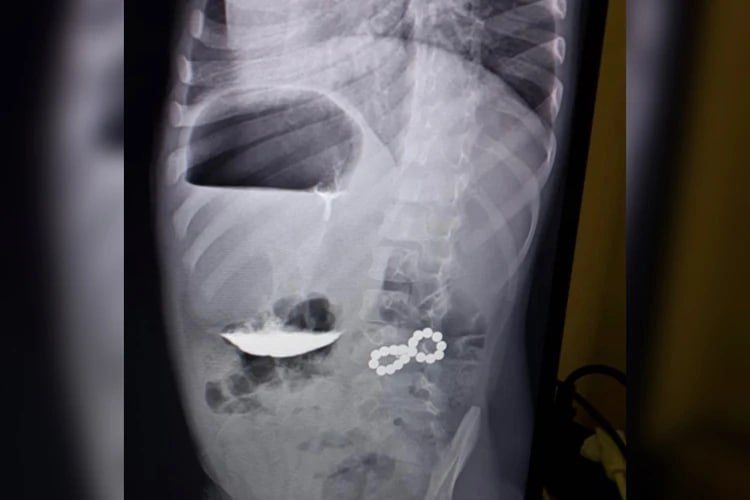

В больницу он поступил с жалобой на кашель. Ребенку назначили рентген легких, но снимок показал неожиданные результаты – в разных петлях кишечника находился целый набор магнитов. Требовалась срочная операция, так как шарики притягивались друг к другу...